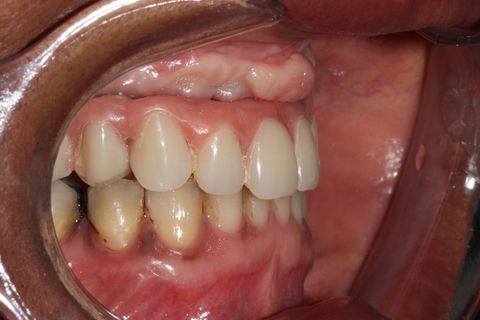

visão lateral

Foi sugerido à paciente tratamento ortodontico da arcada inferior.Ao final desse tratamento, foi confeccionada uma nova prótese fixa com dentes Heraeus Kulzer Premium, nova curva de spee e melhor relação com o corredor bucal.